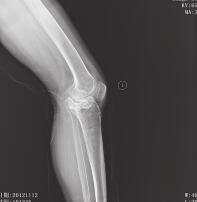

患者,女,59岁,因左膝部骨折术后畸形2年于2012年11月11日入院。约于2年前摔伤左膝部,在当地医院就诊,经X线检查,诊断为“左胫骨平台骨折”,行手术治疗,石膏6周后行膝关节功能锻炼,左膝关节逐渐出现外翻畸形,1年后在当地医院二次手术取出内固定物,左膝关节外翻畸形逐渐加重,感疼痛。入院时查体,左膝关节外翻畸形,局部无明显压痛及骨异常活动,左膝关节伸0°,屈曲90°受限,侧方应力试验阳性,抽屉试验、轴移试验、麦氏试验阴性。X线及CT片(图1、图2)示:左胫骨外侧平台陈旧性骨折,外侧平台前侧关节面塌陷移位明显,部分关节面塌陷达24mm,膝关节退行性改变,膝关节外翻畸形。

图2 术前CT片